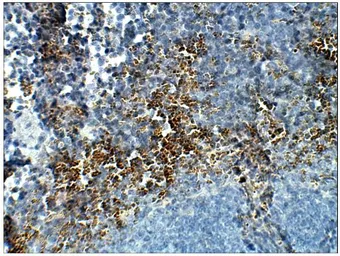

STRA6 antibody

Cat. No. GTX47858

ApplicationsWB IHC-P IP ELISA